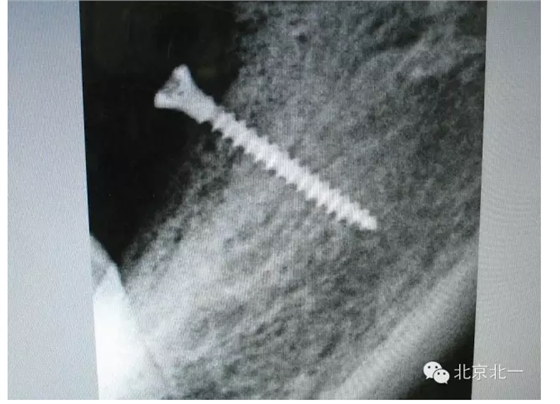

擅長:種植外科,尤其專長復雜牙種植,自體骨移植同期種植,上頜竇底內(nèi)外提升同期種植技術,美學區(qū)種植技術,即刻種植外科與即刻負重技術,軟組織成形外科種植技術及全口無牙頜ALL-ON-FOUR技術,種植并發(fā)癥和種植急癥處置等手術治療,從事口腔頜面外科,正頜外科、頜面部整形、微創(chuàng)拔牙,笑氣無痛舒適種植十余年。